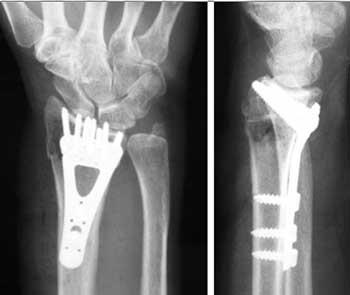

Procedimento. A cirurgia normalmente envolve um corte para acessar diretamente os ossos quebrados e melhorar o alinhamento (redução aberta).

Uma placa e alguns parafusos mantêm os fragmentos quebrados na posição correta até a consolidação.

Dependendo da fratura, há várias opções para manter os ossos na posição correta até a consolidação:

• gesso;

• pinos metálicos (normalmente de aço inoxidável ou titânio);

• placa e parafusos;

• fixador externo (uma estrutura estabilizante colocada do lado externo do corpo para segurar os ossos na posição correta para que possam consolidar);

• qualquer combinação dessas técnicas.